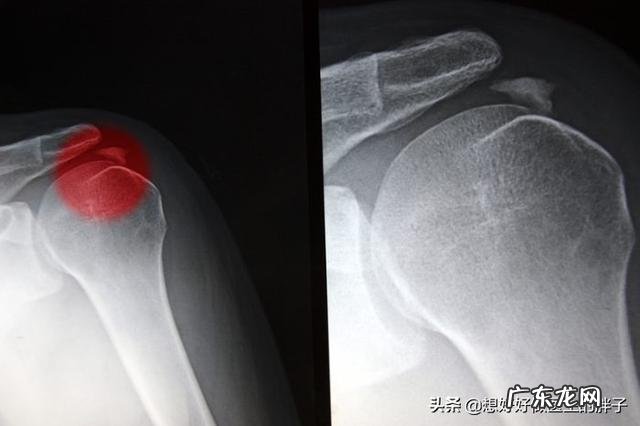

这种情况下首先应该进行肩关节的x线检查,而不是核磁检查,因为钙化灶在x线上显示的更明显,而且检查需要花费的费用低,时间短 。

有一些患者因不明原因在冈上肌肌腱内形成一些钙化性的结构,就像豆腐渣一样包裹在肌腱内,这些结构在生长的过程当中是毫无声息的,有一些患者可能会感觉到肩关节不太舒服,但是达不到疼痛的程度,钙化越来越大,在肩关节活动过程中受到了过度刺激或者是钙化灶慢慢开始吸收的时候,患者往往会表现出急骤的肩关节疼痛,疼痛特别剧烈,难以忍受 。